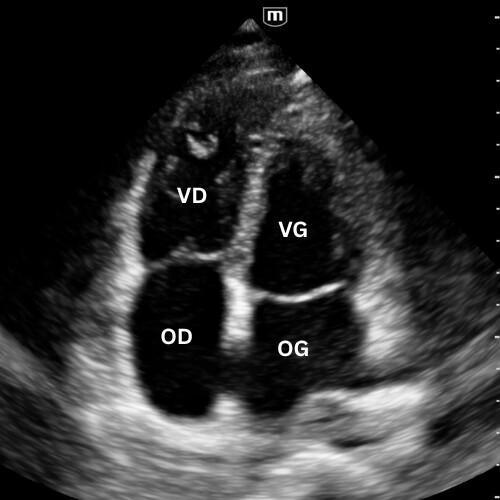

🔹 Vue Apicale Quatre Cavités

Placer la sonde près de l’apex (5e espace, région du mamelon gauche), marqueur vers l’épaule gauche. Glisse légèrement jusqu’à un bon espace intercostal, puis bascule la sonde vers la base du cœur jusqu’à voir VG, VD, OG et OD dans le même plan.

On visualise les quatre cavités, les valves mitrale et tricuspide et le septum.

Permet de comparer VD et VG (surcharge droite si VD ≥ VG), d’apprécier la cinétique globale et de repérer un épanchement péricardique circonférentiel.